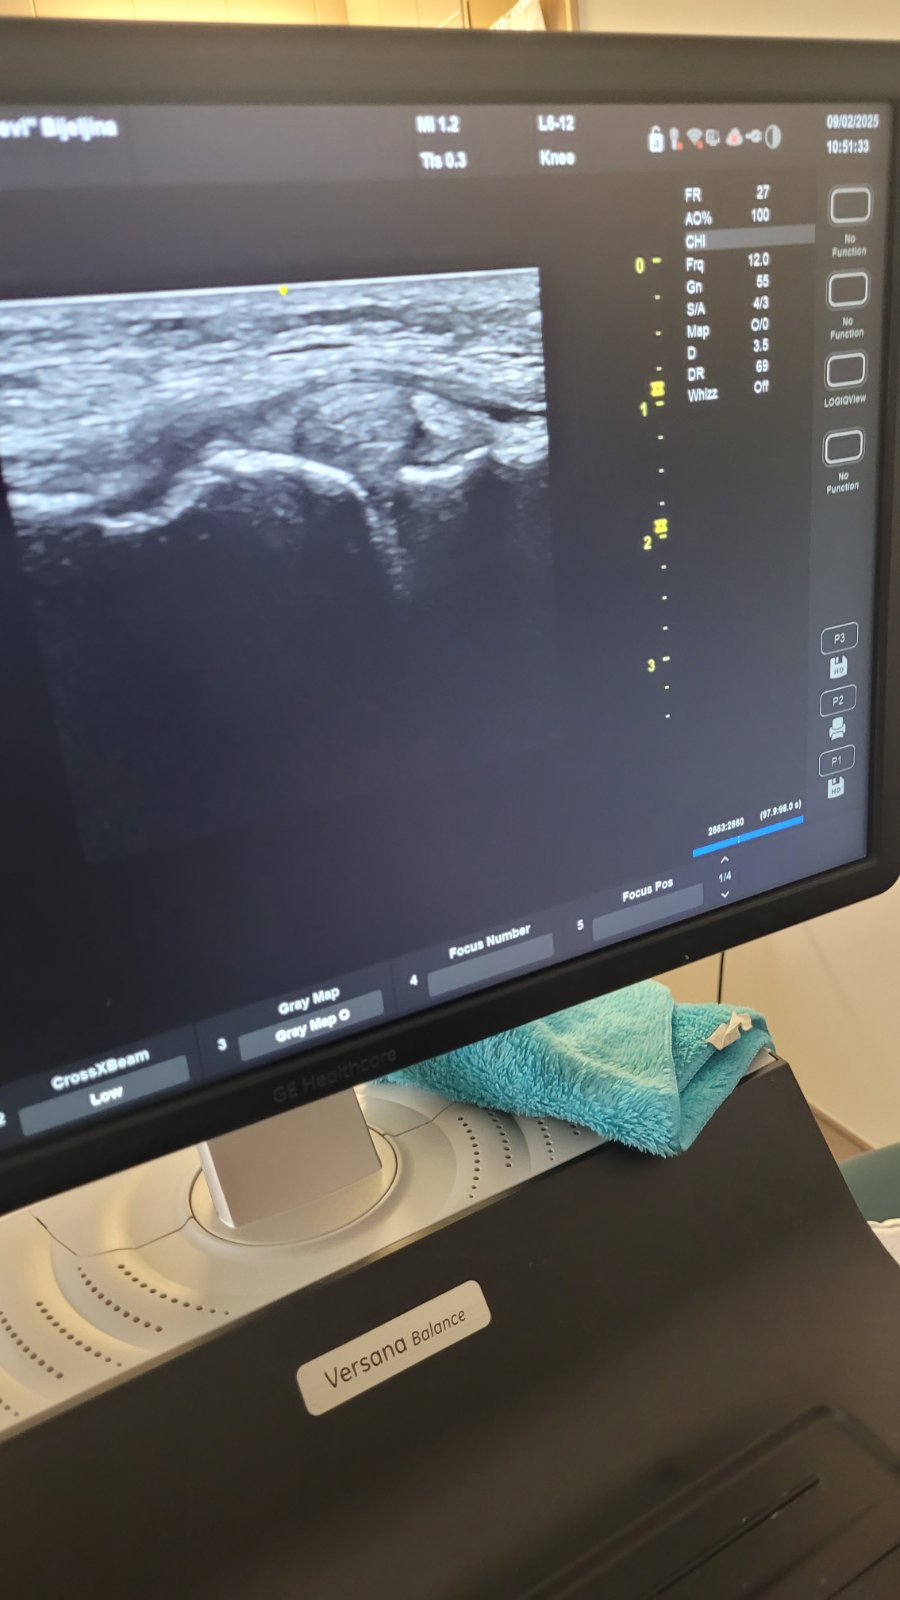

Program je osmišljen u hibridnom formatu, spajajući online teorijska predavanja sa praktičnim radionicama. Polaznici su imali priliku da stiču teorijska znanja iz ultrazvučne dijagnostike putem interaktivnih online predavanja, nakon čega su ih primijenili u kliničkoj praksi tokom trodnevnih radionica u JZU Bolnica “Sveti Vračevi” Bijeljina. Polaznici su dobili priliku da primijene stečena znanja u kliničkoj praksi, usavršavaju tehnike pregleda i razmjenjuju iskustva sa kolegama.

Predavač kursa prof. dr Siniša Ristić, specijalista radiologije, profesor na Medicinskom fakultetu i spoljni saradnik JZU Bolnica “Sveti Vračevi” Bijeljina rekao je da veliko interesovanje i izuzetno pozitivne povratne informacije učesnika potvrđuju značaj ovakvih edukacija za kontinuirani profesionalni razvoj ljekara i da ovakvi program ne samo unapređuju stručne kompetencije, već i doprinose poboljšanju dijagnostike i kvaliteta zdravstvenih usluga.